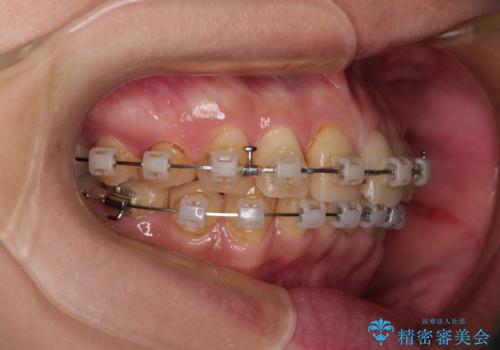

デコボコと乳歯の欠損 ワイヤー矯正とインプラント補綴治療

- 全体的なデコボコと左下乳歯部の欠損を気にして来院された患者様です。

乳歯が抜け落ちた後の後続永久歯が欠損しているため、スペースが残っておりました。

口元の突出感を気にしているのであれば欠損スペースを利用して抜歯矯正を行うことも可能ですが、横顔の印象はスッキリとしている状態であったため、矯正治療でスペースを閉じきることは不可能と判断し、インプラントによる補綴治療を行うこととしました。

第二小臼歯の欠損によるが乳歯残存や欠損が多く、この乳歯は後続永久歯に比べて幅が非常に大きいため、教聖地料によるスペースクローズが難しいことが一般的です。